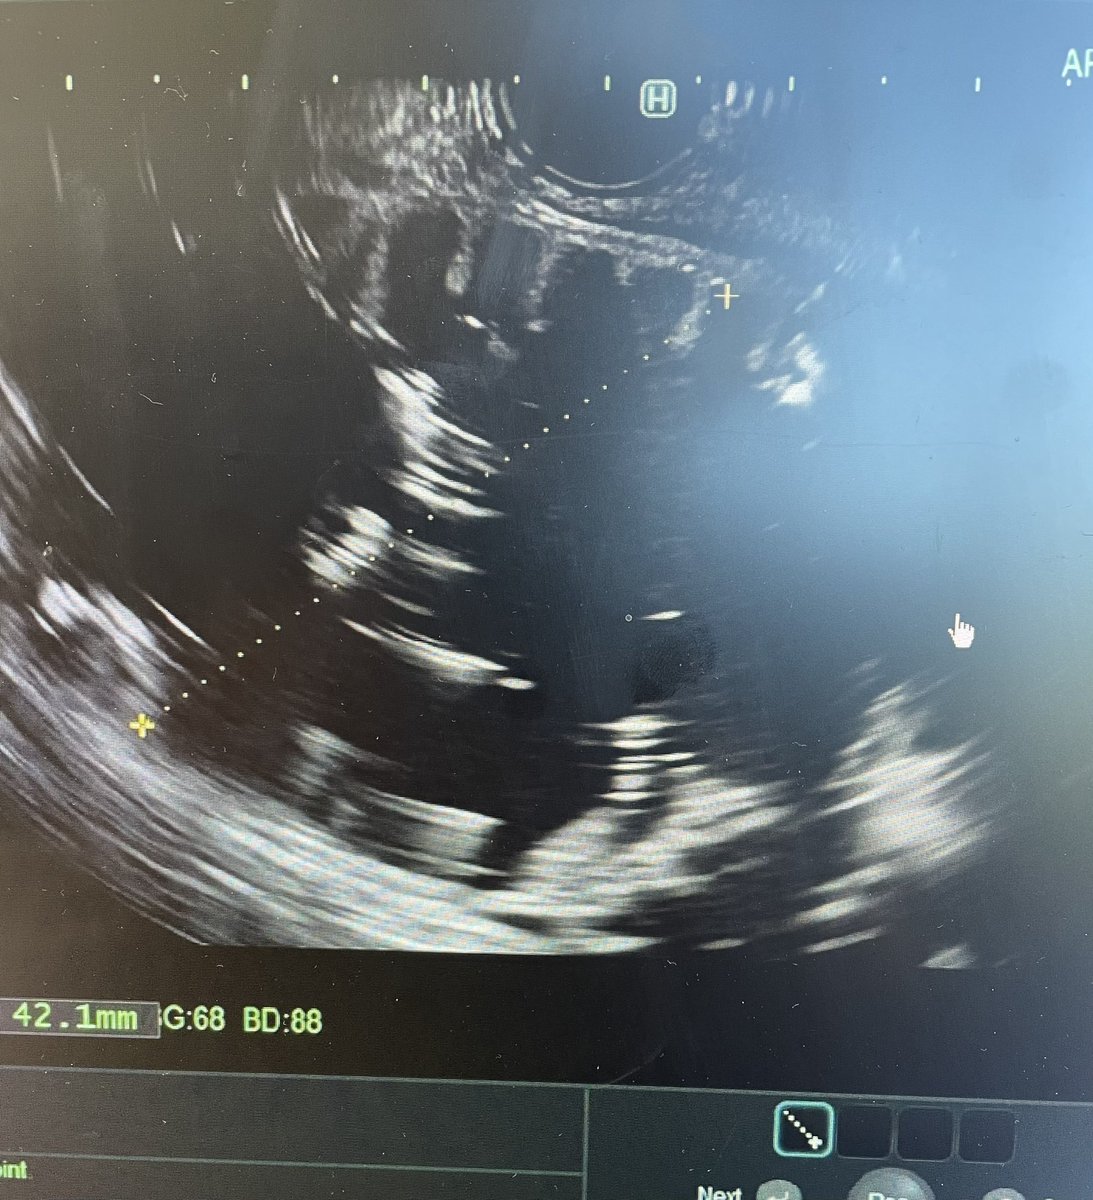

@Bashar_Qumseya Cholangitis with cbd wall thickening ? Stone impacted or papillary stenosis